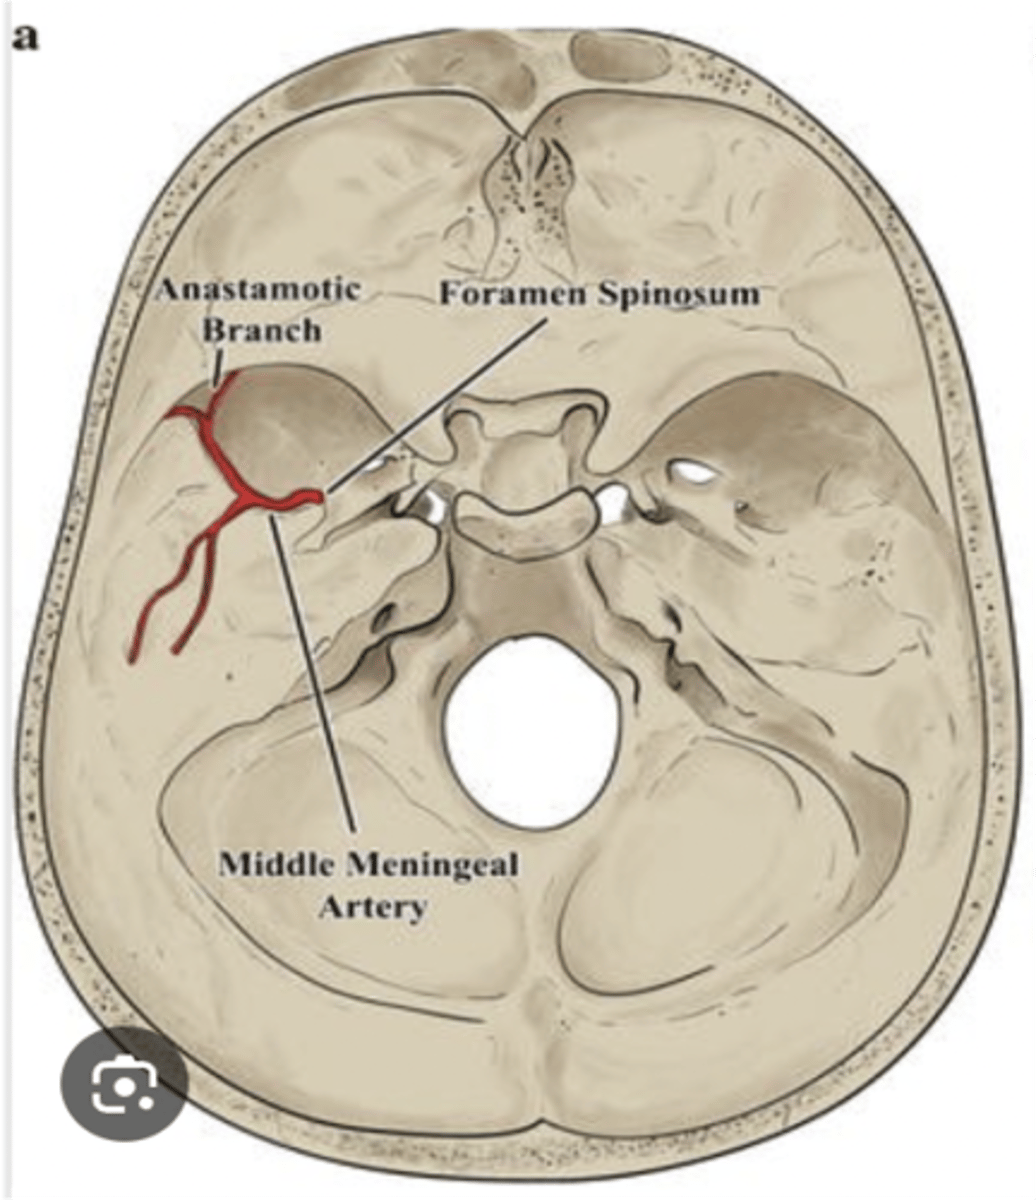

What artery passes through the foramen spinosum?

Middle meningeal artery

The middle meningeal artery passes through what foramen?

Foramen spinosum